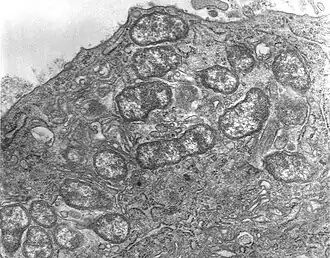

Scrubtyfus is een infectieziekte die wordt veroorzaakt door Orientia tsutsugamushi, een bacterie uit de familie Rickettsiaceae. Deze aandoening komt voor in Azië en noordelijk Australië.